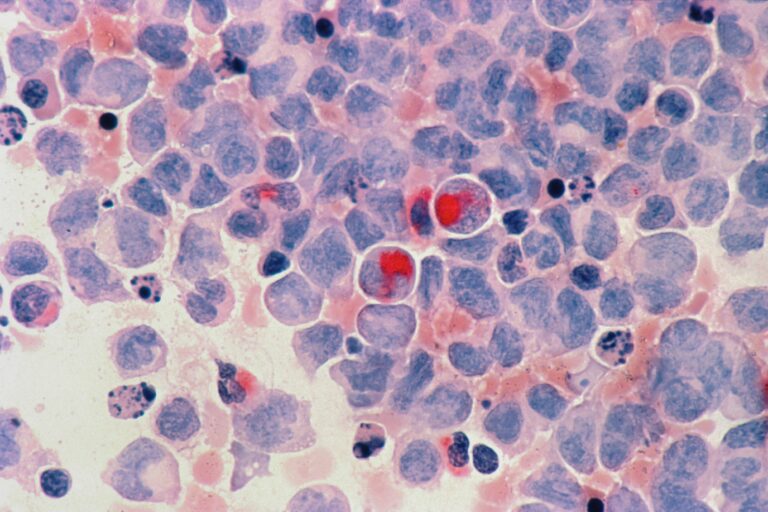

Μια πολύπλοκη σχέση ισορροπίας εν δράσει (Αναδημοσίευση με μετάφραση από: PROJECT CBD, “CANNABIS & THE IMMUNE SYSTEM: A COMPLEX BALANCING ACT” https://www.projectcbd.org/science/cannabis-and-immune-systemBY MARY BILES, ON MAY 08, 2019) Ένα νέο κύμα έρευνας δείχνει ότι τα κανναβινοειδή έχουν ένα προσαρμογόνο, ανοσοδιαμορφωτικό αποτέλεσμα, αντί απλώς να καταστέλλουν την δραστηριότητα του ανοσοποιητικού, όπως νόμιζαν κάποιοι. Η Cannabis sativa καταναλώνεται για λόγους υγείας και διατροφής εδώ και χιλιάδες χρόνια. Πολλοί αρχαίοι πολιτισμοί, από τους Κινέζους μέχρι τους Έλληνες, περιελάμβαναν την κάνναβη στην φαρμακοποιία τους. Τότε, κανείς δεν αμφισβητούσε το πώς ή το γιατί η κάνναβη απαλλάσσει από τον πόνο και ηρεμεί. Ήταν ένας χρήσιμος…